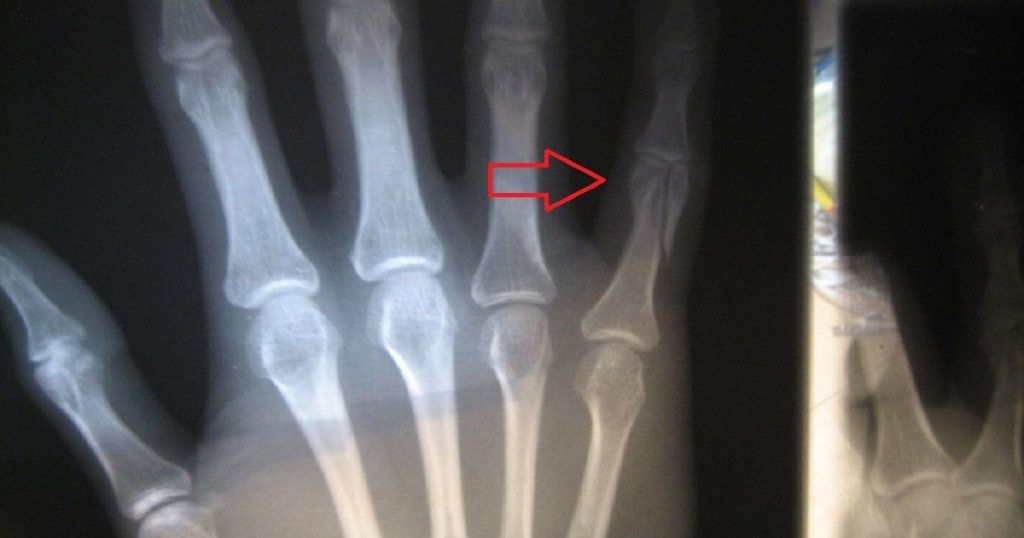

Jari Putus: Apa perlu dibuat dan Rawatan

Apakah cara rawatan awal untuk masalah jari putus? Artikel ini akan membincangkan berkenaan kaedah rawatan yang boleh diberikan kepada mereka […]